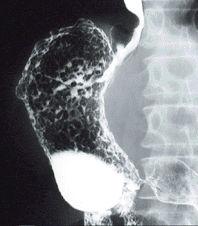

Caso de resección de patología gástrica de tipo inflamatoria que se presentó con hallazgos similares al cáncer avanzado

Enfermedad Inflamatoria - Ulcerativa/otros

estómago(región)/mas de dos

Rayos X